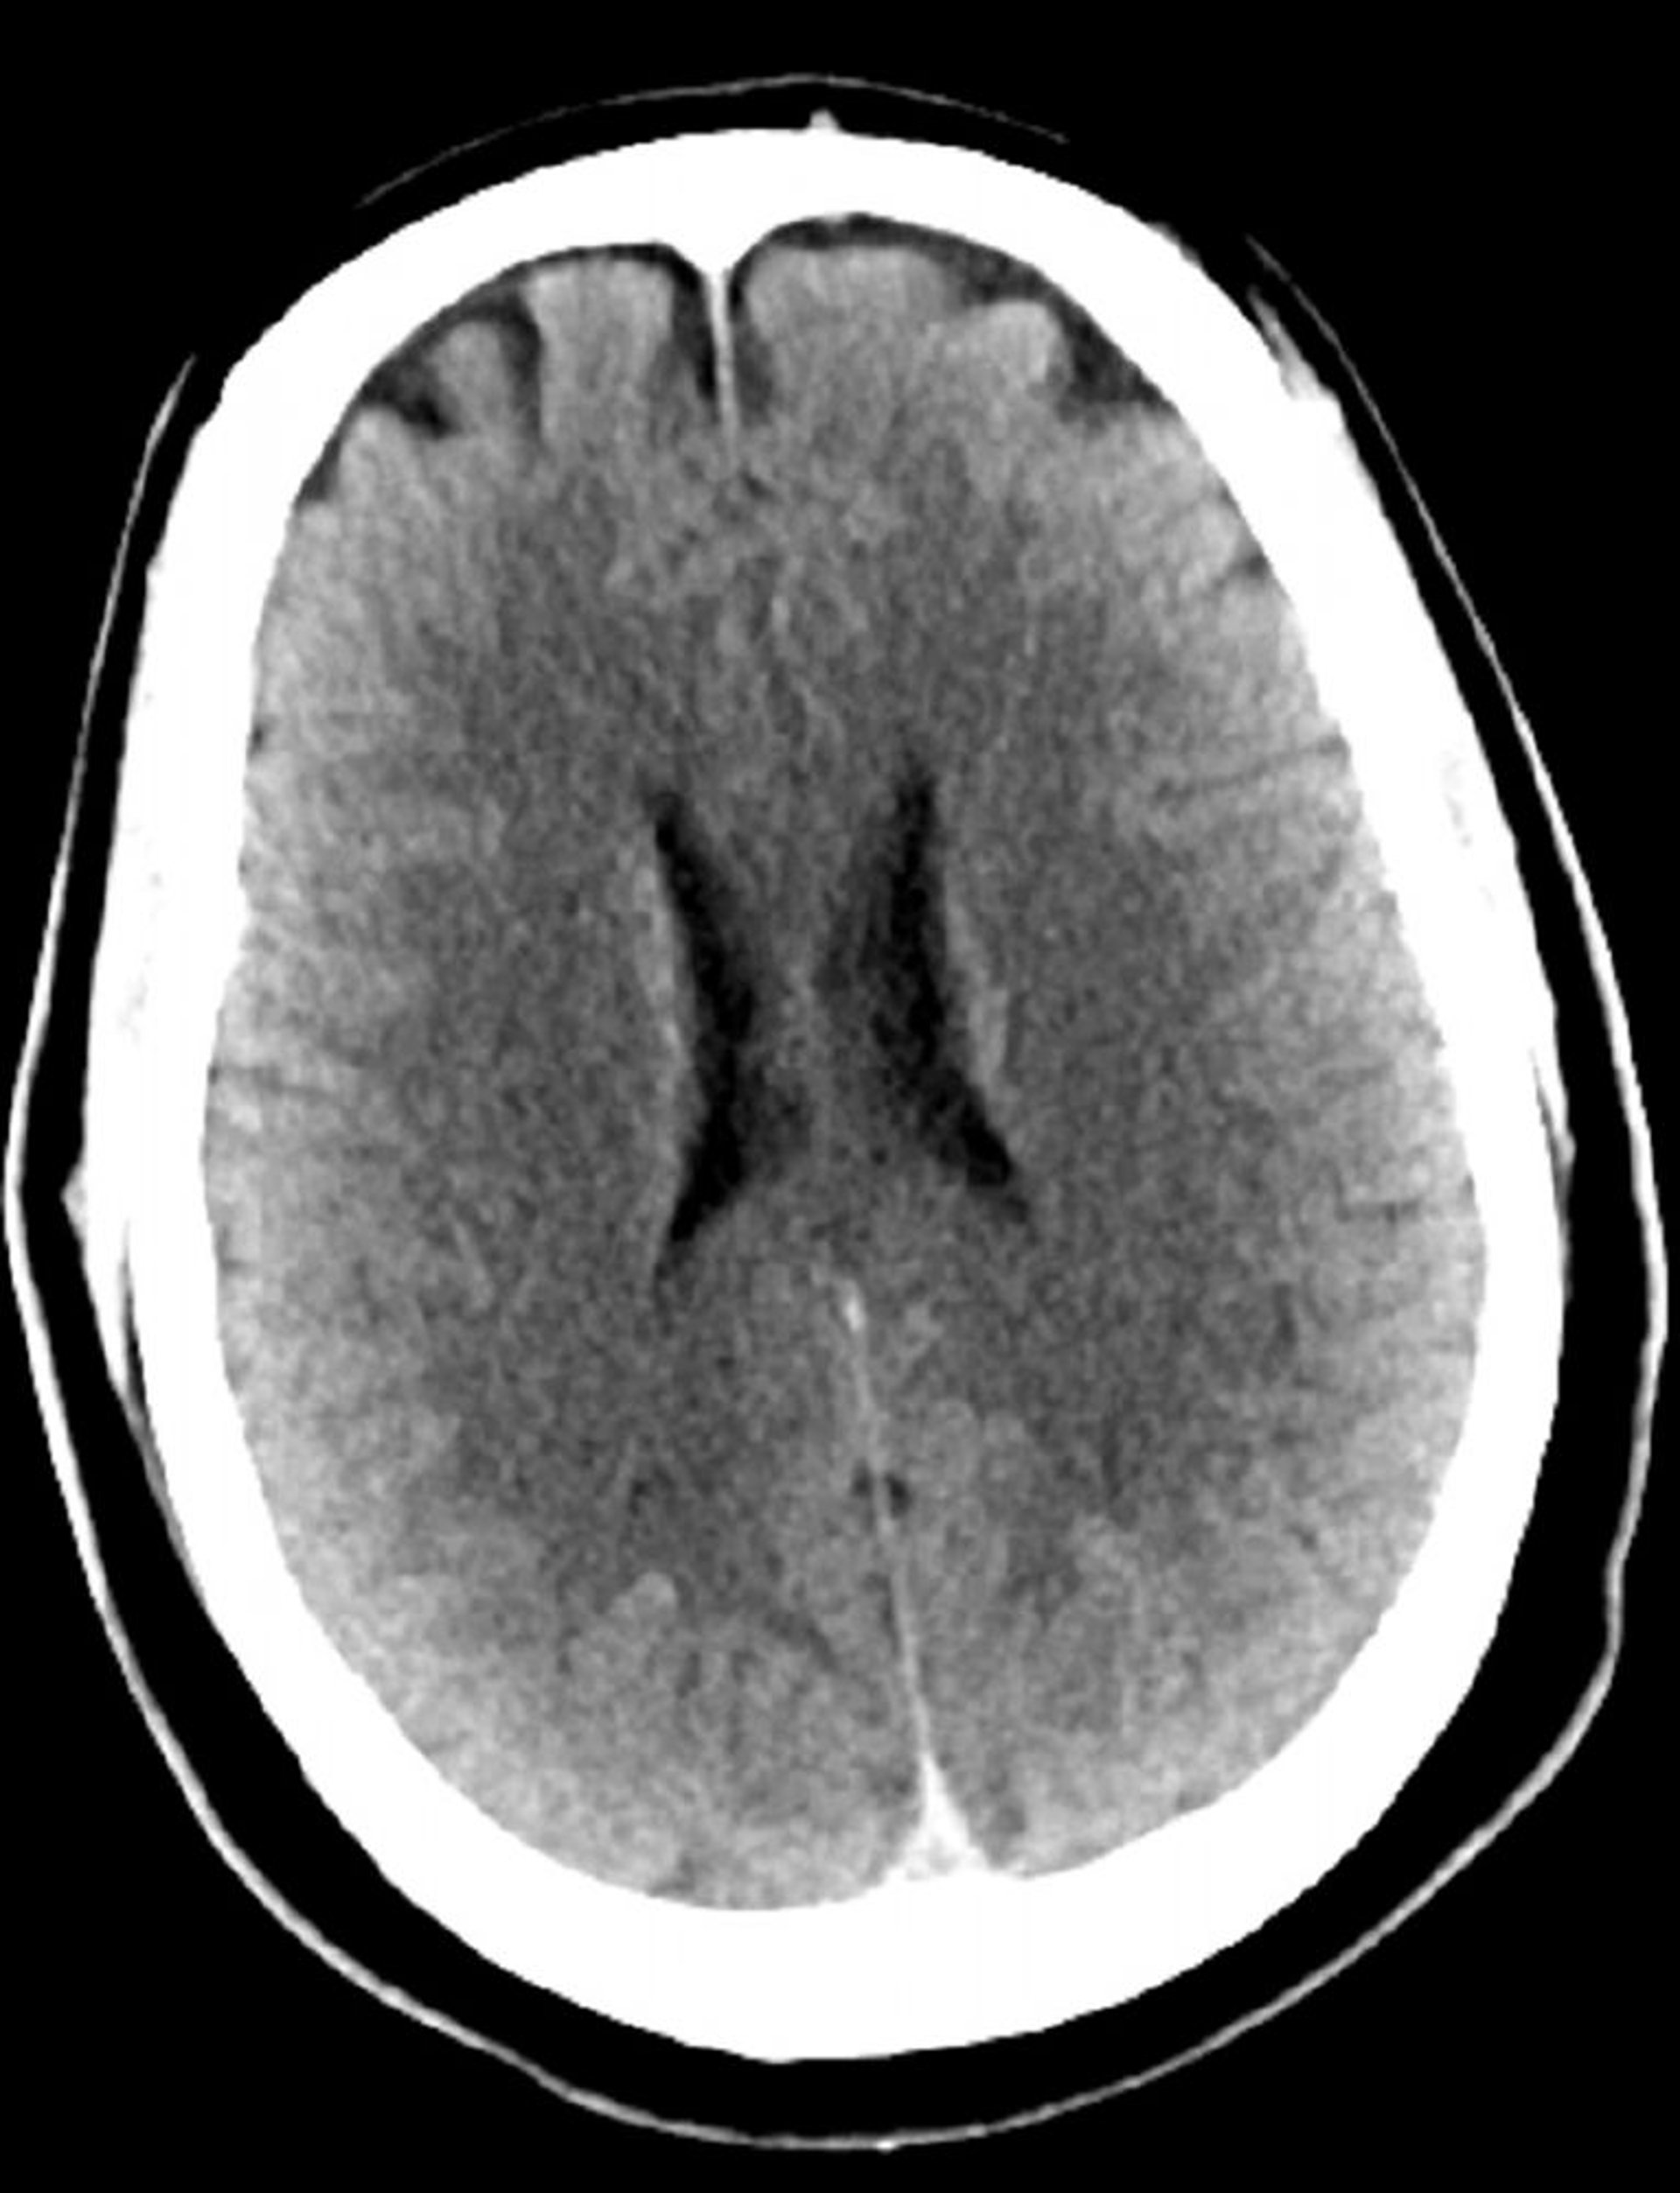

TC cerebrale normale (adulto di 30 anni), slide 3

Questa immagine è una normale TC della testa di un adulto di 30 anni. Non vi è alcun liquido o emorragia intra o extra assiale. La differenziazione grigio-bianca è preservata. Le dimensioni ventricolari e il disegno dei solchi sono normali.